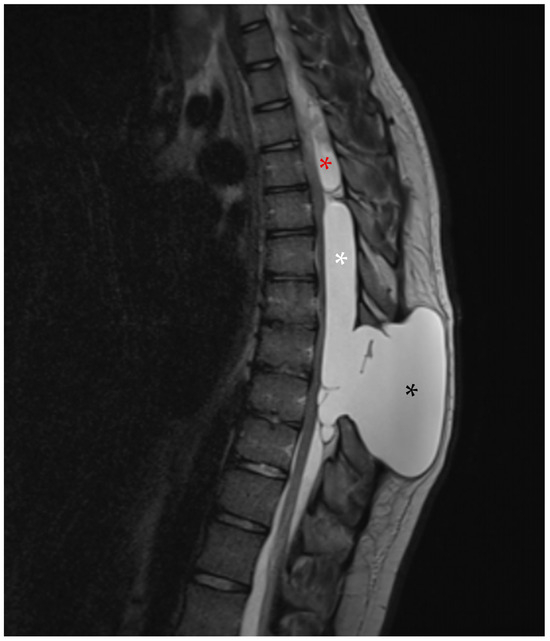

Whole-spine contrast-enhanced Magnetic Resonance Imaging (ceMRI) demonstrated a posterior, extradural intraspinal lesion extending from T2 to T8, causing significant compression of the dural sac and spinal cord (Figure 1). The lesion was formed by two components: a cranial one (T2–T4) and a larger caudal one (T5–T8). The area of maximal spinal cord compression was identified at T7–T8, where subtle intramedullary T2 hyperintensity was observed, suggestive of early spinal cord changes consistent with possible myelopathy (Figure 2). The lesion appeared hyperintense on T2-weighted images, isointense with CSF, and showed no contrast enhancement—findings consistent with a spinal arachnoid cyst.

Figure 1. (A) Cervical spine ceMRI, sagittal section, TSE T2-WI. The cranial portion of the SAC is visible at the T2 level. To facilitate counting, the cervical vertebrae and the first two thoracic vertebrae are marked with their corresponding names. (B) Thoracic spine ceMRI, sagittal section, TSE T2-WI. The SAC is visible in its entirety, composed of a smaller cranial portion (T2–T4, white asterisk) and a larger caudal portion (T5–T8, black asterisk). The dural sac is easily identifiable (white arrows with black outlines), confirming the extradural location.